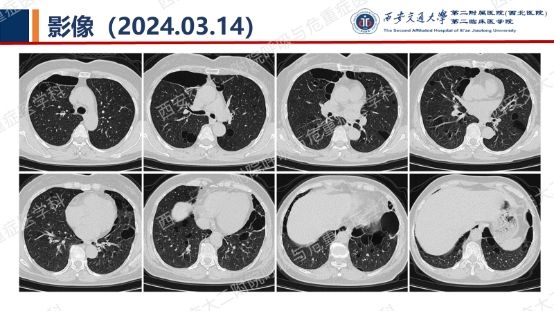

阅影探案,析病寻踪 // 第一期(上)

影像方寸藏玄机,同影异病辨真章。让我们一起抽丝剥茧,揭秘医学真相,解锁临床那些有意思的病例谜题吧!

结合以上患者病史及胸部CT,第一诊断分别考虑???欲知答案,且看后期!!!